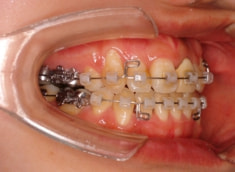

治療開始から約1年後

ご出産のため治療中断期間あり